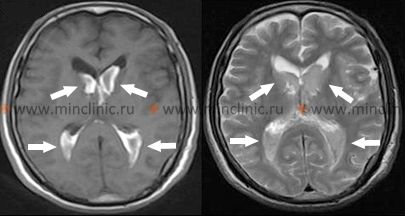

ნათხემის ჰიპერტენზიული ინტრაცერებრული სისხლჩაქცევები

ნათხემში დაწყებული ჰიპერტენზიული სისხლჩაქცევა, როგორც წესი, ვითარდება რამდენიმე საათის განმავლობაში, თუმცა დასაწყისი ზოგჯერ შეიძლება უფრო უეცარი იყოს [1, 2]. ნათხემის სისხლჩაქცევის ადრეული ეტაპის განმასხვავებელი მთავარი მახასიათებელია ის, რომ ცნობიერების საწყისი დაკარგვა იშვიათია, თუ არ არის სწრაფი გაფართოება ტვინის ღეროს კომპრესიით ან მეოთხე პარკუჭში გავრცელება, რაც იწვევს მწვავე ჰიდროცეფალიას [1]. პაციენტები ჩვეულებრივ ვლინდებიან ნათხემის დისფუნქციის ამსახველი სიმპტომებით: ძლიერი თავის ტკივილი (ხშირად კეფის), თავბრუსხვევა ან ვერტიგო, განმეორებითი ღებინება და დგომის ან სიარულის მკვეთრი უუნარობა (ღეროს ატაქსია) [1, 2]. ამ ადრეულმა კლინიკურმა ნიშნებმა ძლიერად უნდა გააჩინოს ეჭვი ნათხემის სისხლჩაქცევაზე, რაც მოითხოვს გადაუდებელ ნეიროვიზუალიზაციას და ნეიროქირურგიულ შეფასებას, რადგან დროული ქირურგიული ჩარევა (ჰემატომის ევაკუაცია) შეიძლება იყოს სიცოცხლის გადამრჩენი და გამოიწვიოს კარგი გამოსავალი, თუ ჩატარდება ტვინის ღეროს მნიშვნელოვანი კომპრესიის დაწყებამდე [1, 5].

მწვავე ფაზაში ნევროლოგიურმა გამოკვლევამ შეიძლება თავდაპირველად გამოავლინოს მინიმალური ან შეუმჩნეველი ფოკალური ნიშნები, ატაქსიისა და ღებინების გარდა [1]. კიდურების აპენდიკულური ატაქსია (მკლავების/ფეხების დისკოორდინაცია) შეიძლება იყოს სისხლჩაქცევის იპსილატერალურად [1]. მზერის პათოლოგიები ხშირია: ჰორიზონტალური მზერის პარეზი (დაზიანების მხარეს ყურების უუნარობა) ან მზერის იძულებითი დევიაცია დაზიანების მხარისგან მოშორებით (კონტრალატერალური დევიაცია) შეიძლება მოხდეს ხიდის მზერის ცენტრების ან გზების ჩართვის გამო [1]. ასევე შეიძლება აღინიშნებოდეს იპსილატერალური პერიფერიული სახის ნერვის (VII) პარეზი ან განმზიდველი ნერვის (VI) პარეზი (რაც იწვევს თვალის განზიდვის დარღვევას) კომპრესიის გამო [1].

სხვა იშვიათად დაფიქსირებული ოკულარული გამოვლინებები მოიცავს ბლეფაროსპაზმს (ქუთუთოს უნებლიე დახურვა), ცალმხრივი ქუთუთოს დახურვას ან skew დევიაციას (თვალების ვერტიკალური ასიმეტრია) [1]. ოკულარული ბობინგი (თვალის სპონტანური, სწრაფი მოძრაობები ქვემოთ, რასაც მოჰყვება ნელი დრიფტი ზემოთ), რომელიც ტიპურად ასოცირდება ხიდის მძიმე დაზიანებასთან, შეიძლება მოგვიანებით მოხდეს, თუ ცნობიერება გაუარესდება და გადავა კომაში ტვინის ღეროს კომპრესიის გამო [1]. ვერტიკალური თვალის მოძრაობები, როგორც წესი, შენარჩუნებულია გვიან სტადიებამდე [1]. გუგები, როგორც წესი, რჩება მცირე, მაგრამ რეაგირებს სინათლეზე, სანამ ტვინის ღეროს მნიშვნელოვანი კომპრესია არ მოხდება [1]. ხშირად აღინიშნება იპსილატერალური სახის სისუსტე (ხშირად პერიფერიული ტიპის VII ნერვის პარეზი) და დაქვეითებული რქოვანას რეფლექსი იმავე მხარეს [1].

კონტრალატერალური ჰემიპლეგია და ცენტრალური ტიპის სახის სისუსტე, როგორც წესი, არ არსებობს სუფთა ნათხემის სისხლჩაქცევის დროს, რაც ეხმარება მის გარჩევას სუპრატენტორიული სისხლდენებისგან[1]. იშვიათად, ტვინის ღეროს მძიმედ კომპრესირებადი დიდი ნათხემის სისხლჩაქცევები შეიძლება გამოვლინდეს ტეტრაპლეგიით მაშინ, როცა ცნობიერება თავდაპირველად შენარჩუნებულია, ან სპასტიური პარაპარეზით [1]. პლანტარული რეფლექსები (ბაბინსკის ნიშანი) თავდაპირველად შეიძლება იყოს ფლექსორული (მომხრელი), მაგრამ შეიძლება პროგრესირდეს ექსტენზორულ (გამშლელ) პასუხებამდე, როდესაც ტვინის ღეროს ფუნქცია უარესდება [1]. ნათხემის სისხლჩაქცევის მთავარი საფრთხეა უეცარი ნევროლოგიური დაქვეითება სტუპორსა და კომაში, პროგრესირებადი ტვინის ღეროს კომპრესიის ან მეოთხე პარკუჭის ობსტრუქციის შედეგად მწვავე ჰიდროცეფალიის გამო [1, 5]. მას შემდეგ, რაც მოხდება ტვინის ღეროს მნიშვნელოვანი კომპრესია, თერაპიული ან ქირურგიული ჩარევები ხშირად ბევრად ნაკლებად ეფექტურია [1].

- ნათხემის სისხლჩაქცევა: ხშირად იპსილატერალური მზერის პარეზი ან კონტრალატერალური მზერის დევიაცია, მაგრამ ტიპურად მნიშვნელოვანი კონტრალატერალური ჰემიპარეზის გარეშე თავდაპირველად.